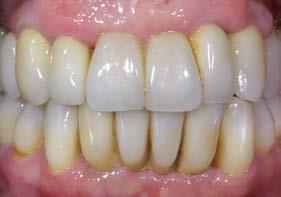

Tratamiento de caninos retenidos superiores en paciente en crecimiento con clase II división 2. Reporte de caso clínico

Los caninos retenidos constituyen una alteración eruptiva frecuente, con mayor prevalencia en la arcada superior. Su etiología es multifactorial y puede interferir con el trayecto normal de erupción, comprometiendo la oclusión y la estética.

Objetivo: Corregir una maloclusión Clase II división 2 mediante tratamiento ortodóntico en un paciente en crecimiento con ambos caninos superiores retenidos. Metodología: Se presenta el caso de un paciente masculino de 12 años, en dentición permanente, con perfil convexo, patrón dolicofacial y Clase II esquelética. Se realizó tratamiento ortodóntico sin extracciones. Para la tracción y alineación de los caninos retenidos se emplearon resortes abiertos (open coil springs) para la creación de espacio. Resultados: